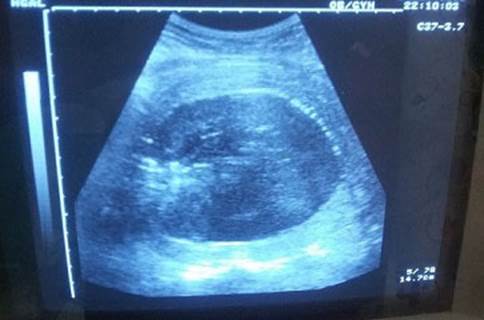

Se extrajo recién nacido femenino con test de Apgar 8/9 y peso de 4025 g. Se realizó alumbramiento activo y se constató hemorragia obstétrica mayor por atonía uterina (pérdida aproximada del 25 % de la volemia), refractaria al tratamiento médico y se decidió realizar manejo conservador del útero, mediante el taponamiento endouterino con balón de Bakri. En el propio salón de partos se realizó reposición volumétrica con cristaloides y protocolos de transfusión masiva (glóbulos, plasma y plaquetas) en correspondencia con el grado de shock diagnosticado (leve). Se comprobó mediante ecografía abdominal la colocación adecuada del balón y se logró contractilidad uterina y hemostasia. (Figuras 1 y 2). Finalizó el procedimiento sin otras complicaciones y luego de alcanzar la estabilidad hemodinámica de la paciente, esta fue trasladada a Unidad de Cuidados Intensivos Polivalentes, para mejor seguimiento de su condición.